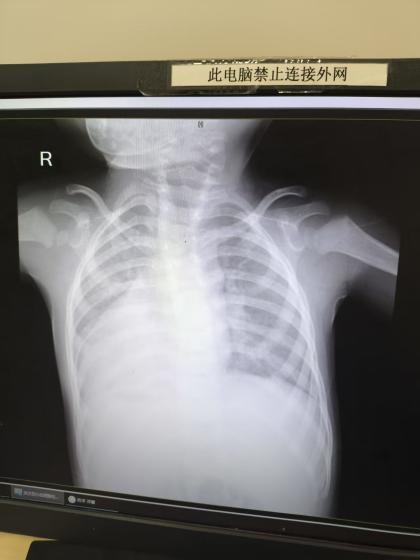

结合病史检查后,轩轩被确诊为室间隔缺损、房间隔缺损以及心室流出道狭窄等先心病。与常人不同的是,小患儿的心脏及肝脾胃等器官都长在身体右侧,犹如照镜子一般翻转,所以叫做镜面人。这是一种先天畸形,内脏器官与正常解剖位置呈镜像分布,发生率仅为 12 万分之一。

「武侠剧里有被刺中胸腔要害却能逢凶化吉的角色,令人不可思议。其实生活中,右心人的确存在。正常人心脏居胸腔偏左,而极少部分人的心脏和其它器官犹如『天生反骨』,全都『溜』到了右侧。单纯的镜像右位心若没有结构异常,也是健康人,但这名患儿还有室缺、房缺等问题。」王潇主任说道。